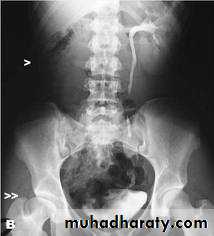

IVU shows

1. The kidneys at low position .

2.Close to the spine with long axis parallel to the spine .

3. Malrotation manifested by medially directed calyces.

4- The renal pelvis and ureters are anterior and lateral in position .